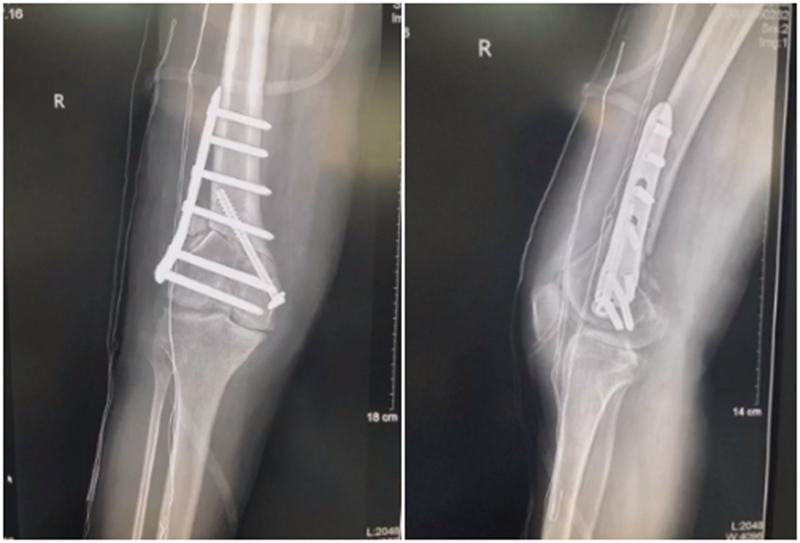

病例,X患者,女,双侧外翻膝,行双侧DFO。

术后6周摔伤,一侧出现膝内翻。

影像学检查显示左侧出现合页断裂。

进行翻修,术前力线显示内翻。

术中发现螺钉松动,截骨端出现坎插迹象。

近端螺钉松开,调整力线,重新固定后,在外侧加小钢板抗旋

术后10周复查,力线较好。